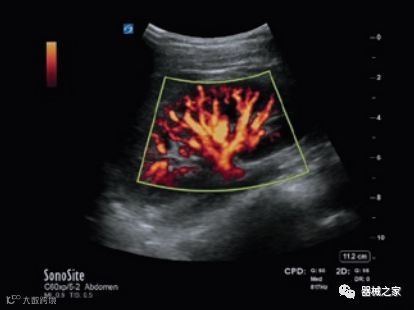

GE Healthcare用于胎儿超声的胎儿心脏和血管分析软件,在Voluson E10上提供,有助于在不到三分钟的时间内评估胎儿的心脏形状,大小和收缩性。称为辐射流的功能以三维视图显示血流。它还可以帮助显示缓慢流动的血液,例如神经血管循环。

Voluson E10